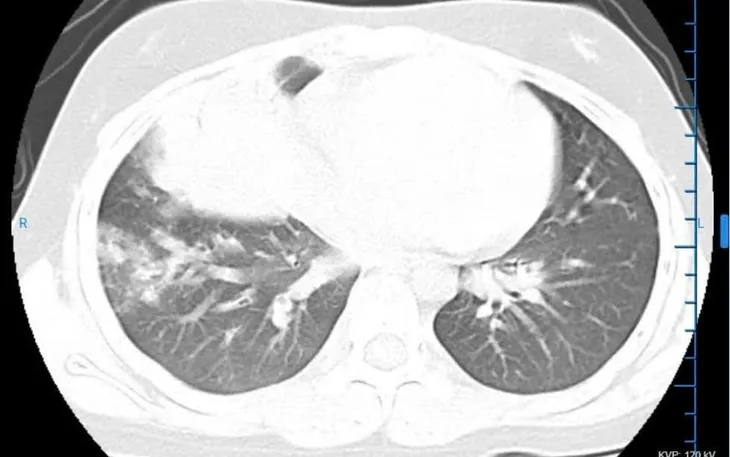

Phác đồ điều trị bao gồm sử dụng kháng sinh phù hợp theo hướng viêm phổi, kết hợp hạ sốt, bù dịch, thuốc long đờm và theo dõi sát diễn biến hô hấp cũng như toàn trạng của bệnh nhi. Trong quá trình điều trị, đội ngũ bác sĩ, điều dưỡng thường xuyên đánh giá đáp ứng thuốc, kịp thời điều chỉnh để bảo đảm hiệu quả và an toàn.

Sau khoảng 2 tuần điều trị, tình trạng bệnh nhi cải thiện rõ rệt: hết sốt, giảm ho, sức khỏe ổn định, ăn uống tốt hơn và phục hồi tốt. Bệnh nhi đã được cho xuất viện trong tình trạng an toàn.